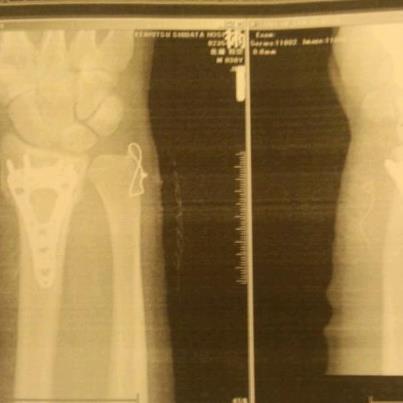

▼ 手首骨折の経過

■1月1日

妙高杉ノ原のレイルでフェイキーFS270Slideの着地失敗で呆気なく、

右手首の橈骨遠位端骨折&尺骨茎状突起骨折・・・・

リストガードしていたのに肘から手首間にある2本の骨2つとも

折れちゃいました。

それもスキー場近くの病院に応急処置してもらってレントゲン撮ってもらったところ、

出来るだけ早めに手術した方がいいとのこと・・・

■1月10日

人生初オペ+入院

部分麻酔でプレートを固定するために骨に穴を開ける音+振動で

ハンパなく、怖かったです。

それも20回くらい「ウィーンウィーン」とドリル音がして、何個穴

開けるのよ・・・と聞きたくなるほど不安だったけど、

何よりも尿漏れとの激闘でした(笑)

3時間でオペ終了。